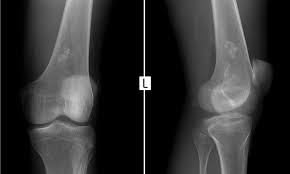

육종암 의심 증상은 해당 부위 통증이라고 한다. 다리, 골반 등이 아프다고 한다. 가벼운 운동이나 스트레칭을 하다가 뼈에 금이 가거나 골절이 생겨 엑스레이 사진을 찍어 발견하는 경우도 있다고 한다.

해당 부위 없던 통증이 1주일 이상 지속되면 검사를 받아보라는 게 전문의들의 의견이라고 한다.